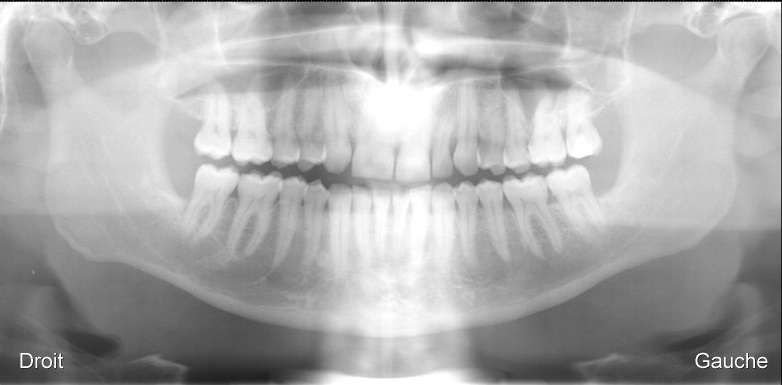

La fusion, ou synnodontie fait que 2 dents sont soudées entre elles. Ce sont souvent des incisives, soit définitives soit temporaires . Il s’agit là d’anomalie de la couronne et de la racine

Incisives centrale 11 et latérale 12 soudée en une seule dent.

Radiographie panoramique du même parient: 11-12 soudée en une seule dent.

Radiographie panoramique du même patient: 11-12 soudée en une seule dent.